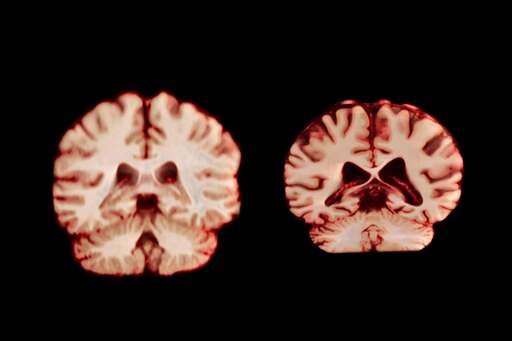

Men’s Brains Shrink Faster than Women’s. What That Means for Alzheimer’s

Women’s brains age more slowly than men’s, but they still have higher rates of Alzheimer’s disease